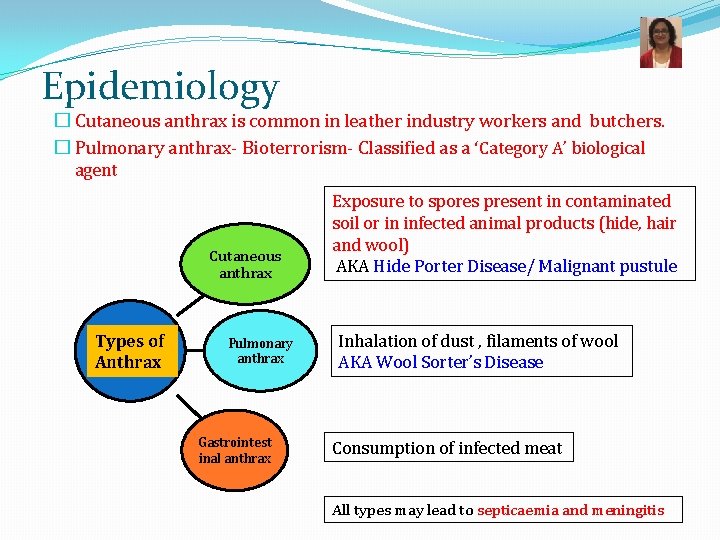

Epidemiology � Cutaneous anthrax is common in leather industry workers and butchers. � Pulmonary anthrax- Bioterrorism- Classified as a ‘Category A’ biological agent Cutaneous anthrax Types of Anthrax Pulmonary anthrax Gastrointest inal anthrax Exposure to spores present in contaminated soil or in infected animal products (hide, hair and wool) AKA Hide Porter Disease/ Malignant pustule Inhalation of dust , filaments of wool AKA Wool Sorter’s Disease Consumption of infected meat All types may lead to septicaemia and meningitis